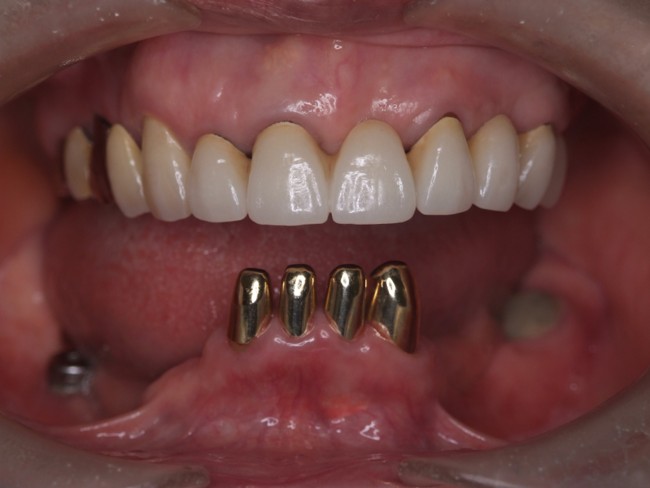

| 主訴 | 50代男性 右上の歯と歯茎が痛い。どこで噛んでいいのか分からないので夜も眠れない |

| 治療内容 | 外科矯正治療・インプラント治療・セラミック治療を行いました。 |

| 治療費 | 4,500,000円(税込み) |

| 治療期間 | 4年(矯正治療期間 3年) |

| 治療回数 | 60回 |

| 想定されたリスク | 顎骨の変形があったので、全身麻酔下による外科処置が必要になり、身体的、精神的負担が増す可能性がありました。 清掃状況によっては矯正中にむし歯が発生するリスクがありました。 |